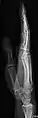

- Radius and Ulna - AP and Lateral

- Wrist - DP and Lateral